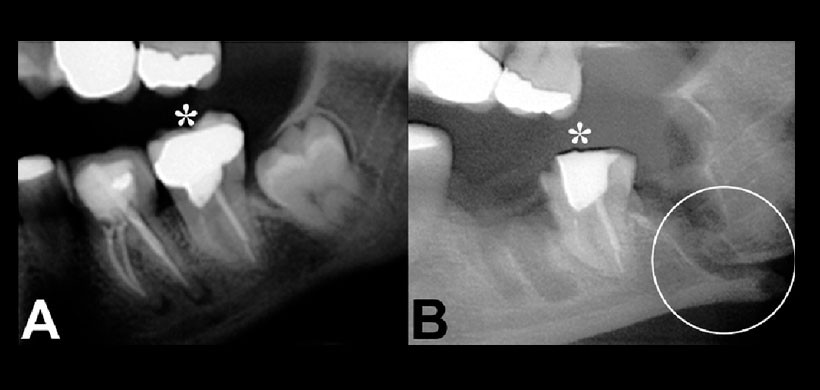

Fig 1. Ejemplos de la insuficiente cobertura de imágenes que brindan las radiografías intraorales (periapical). (A) Sólo la corona del tercer molar se muestra en la imagen; (B) la punta de la raíz distal no se muestra en la imagen y el canal mandibular no puede ser interpretado. Se debe considerar a la radiografía panorámica como un examen que brinde una mayor cobertura de imagen.

Fig 2. Paciente sexo femenino de 44 años con antecedentes de osteopenia y signos de fractura mandibular consecuente a extracción de primer y tercer molares inferiores izquierdos. A: Radiografía prequirúrgica; B: Radiografía postquirúrgica donde pueden observarse ambos alveólos postextracción, fractura desfavorable con desplazamiento del ángulo mandibular a la altura del alvéolo del tercer molar y discontinuidad del canal para el nervio alveolar inferior (círculo) e irregularidad por fractura coronaria del segundo molar (*), resultado de maniobras técnicas excesivas y descontroladas. Pudo corroborarse daño irreversible al nervio alveolar inferior con hiperestesia dolorosa en la hemimandíbula izquierda y parestesia en el hemilabio izquierdo